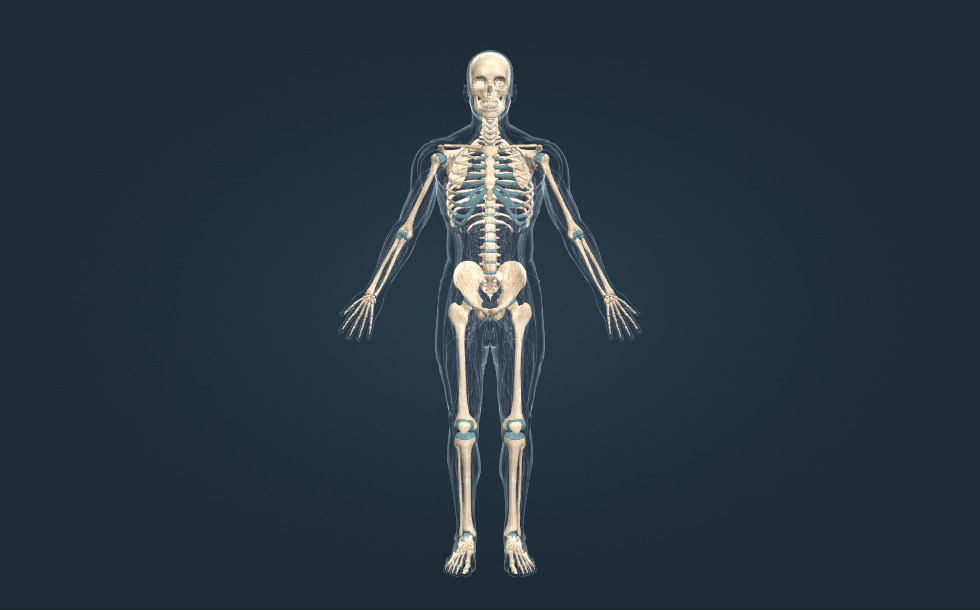

Bộ xương

- hộp sọ - Nó chứa bộ não.

- cột sống - Nó chứa tủy sống.

- khung chậu

- các xương chi trên

- các xương chi dưới

- ngực

Bộ xương của người trưởng thành gồm 206 chiếc xương. Xương vừa cứng, vừa dẻo để có thể mang một trọng lượng lớn. Chuyển hóa của xương diễn ra chậm, do đó khi bị gãy, xương liền lại khá chậm. Một xương bị gãy cần ít nhất 6 tuần để liền lại. Để phòng ngừa loãng xương, chúng ta cần nạp một lượng canxi thích hợp hàng ngày (1.500 mg cho thanh thiếu niên).

Bộ xương của người trưởng thành gồm 206 chiếc xương. Xương vừa cứng, vừa dẻo để có thể mang một trọng lượng lớn. Chuyển hóa của xương diễn ra chậm, do đó khi bị gãy, xương liền lại khá chậm. Một xương bị gãy cần ít nhất 6 tuần để liền lại. Để phòng ngừa loãng xương, chúng ta cần nạp một lượng canxi thích hợp hàng ngày (1.500 mg cho thanh thiếu niên).